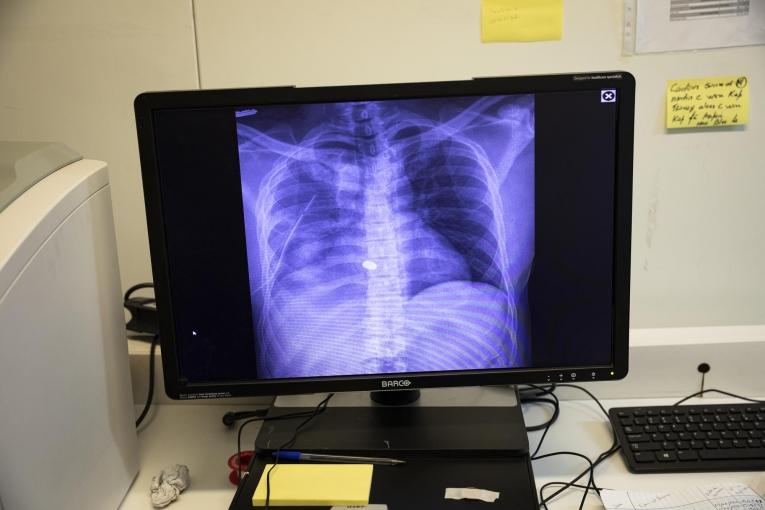

Au cours des trois mois qui ont suivi son ouverture, l'hôpital de traumatologie de Tabarre, géré par Médecins Sans Frontières (MSF) à Port-au-Prince, a admis plus de 360 patients nécessitant des soins vitaux, dont plus de 220 patients blessés lors des épisodes de violence dans la capitale.

En trois mois, l'équipe de traumatologie a pris en charge des patients de nombreux quartiers de Port-au-Prince et des alentours ; principalement pour des blessures par balle et des accidents de la circulation.